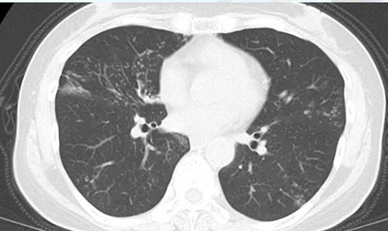

ちなみにCT画像はこんな感じです。

上葉舌区・中葉:主に肺の右中葉と左舌区に病変が集中することが多いです。

多発性の小結節影:両側の肺野に、小さな粒状の影が多数見られます。

気管支拡張像:肺の末梢にある気管支が拡張し、線路の線路やリングのような影として認められます。

本症例は、右中肺野外側、右下肺野に粒状影を認め、NTMを疑います。

同所見を認めた場合、当然精査しますが、副鼻腔気管支炎症候群(SBS)の可能性もあるため、喀痰検査で菌を同定して確定診断を行います。